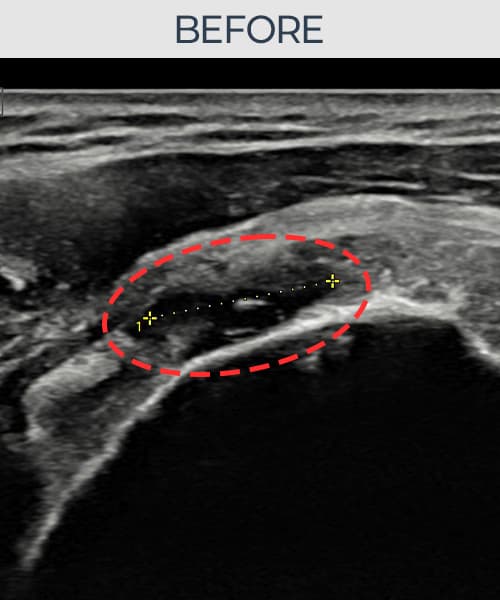

[촬영시기:23.07.31~23.09.27]

[어깨인대 축소봉합술] 좌측 어깨 극상근건 광범위 파열로 수개월간 일상생활이 어렵던 중 내원하셨습니다.